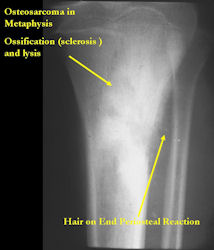

Radiographic Presentation: Conventional Osteosarcoma

There are 3 radiographic presentations for osteosarcomas, depending upon the amount of osteoid/ossification and calcium deposition:

- Mixed sclerotic and lytic, permeative lesion most common radiographic presentation

- Purely osteoblastic, permeative lesion: dense sclerosis and osteoid production

- Purely lytic, permeative lesion: little osteoid production and/or minimal calcium deposition in osteoid

Conventional osteosarcomas are permeative lesions on plain radiographs (borders of the lesion cannot be clearly delineated)

- Wide zone of transition from lytic/sclerotic areas of tumor to normal bone

- Makes borders of lesion hard to define

- Most (90%) arise from the metaphysis of the bone

- Rarely (10%) arise from the diaphysis

- Most conventional osteosarcomas (90-95%) extend through the bone into the soft tissues and form a soft tissue mass outside of the bone